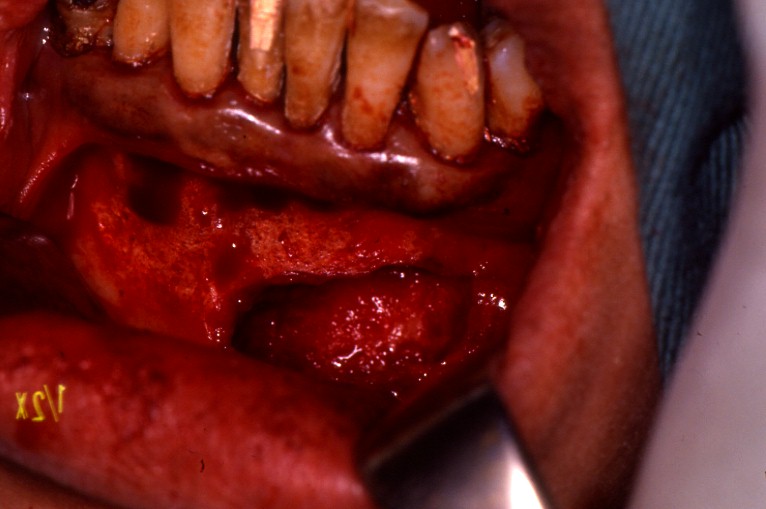

下顎小臼歯部に発生した歯根嚢胞。

局所麻酔下に嚢胞摘出術、歯根端切除術を行いました。

原因歯は抜歯することなく、保存できました。